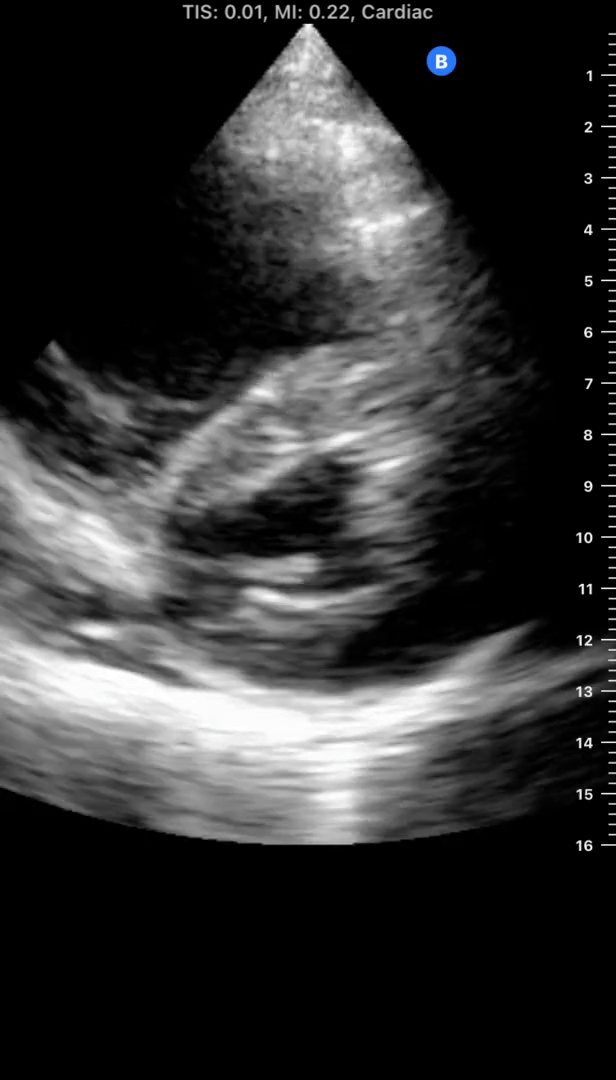

The name of this sign

12

1 pts

The location of abnormal fluid